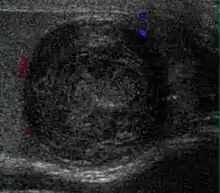

Patients with testicular lymphoma are usually old aged around 60 years of age, present with painless testicular enlargement and less commonly with other systemic symptoms such as weight loss, anorexia, fever and weakness. Bilateral testicle involvements are common and occur in 8.5% to 18% of cases. At sonography, most lymphomas are homogeneous and diffusely replace the testis [Fig. 7]. However focal hypoechoic lesions can occur, hemorrhage and necrosis are rare. At times, the sonographic appearance of lymphoma is indistinguishable from that of the germ cell tumors [Fig. 8], then the patient's age at presentation, symptoms, and medical history, as well as multiplicity and bilaterality of the lesions, are all important factors in making the appropriate diagnosis.

However, these patterns, except the latter one, may be considered as non-specific as heterogeneous echotexture and shadowing calcification can also be detected in malignant testicular tumors. The onion peel pattern of epidermoid cyst [Fig. 10] correlates well with the pathologic finding of multiple layers of keratin debris produced by the lining of the epidermoid cyst. This sonographic appearance should be considered characteristic of an epidermoid cyst and corresponds to the natural evolution of the cyst. Absence of vascular flow is another important feature that is helpful in differentiation of epidermoid cyst from other solid intratesticular lesions.